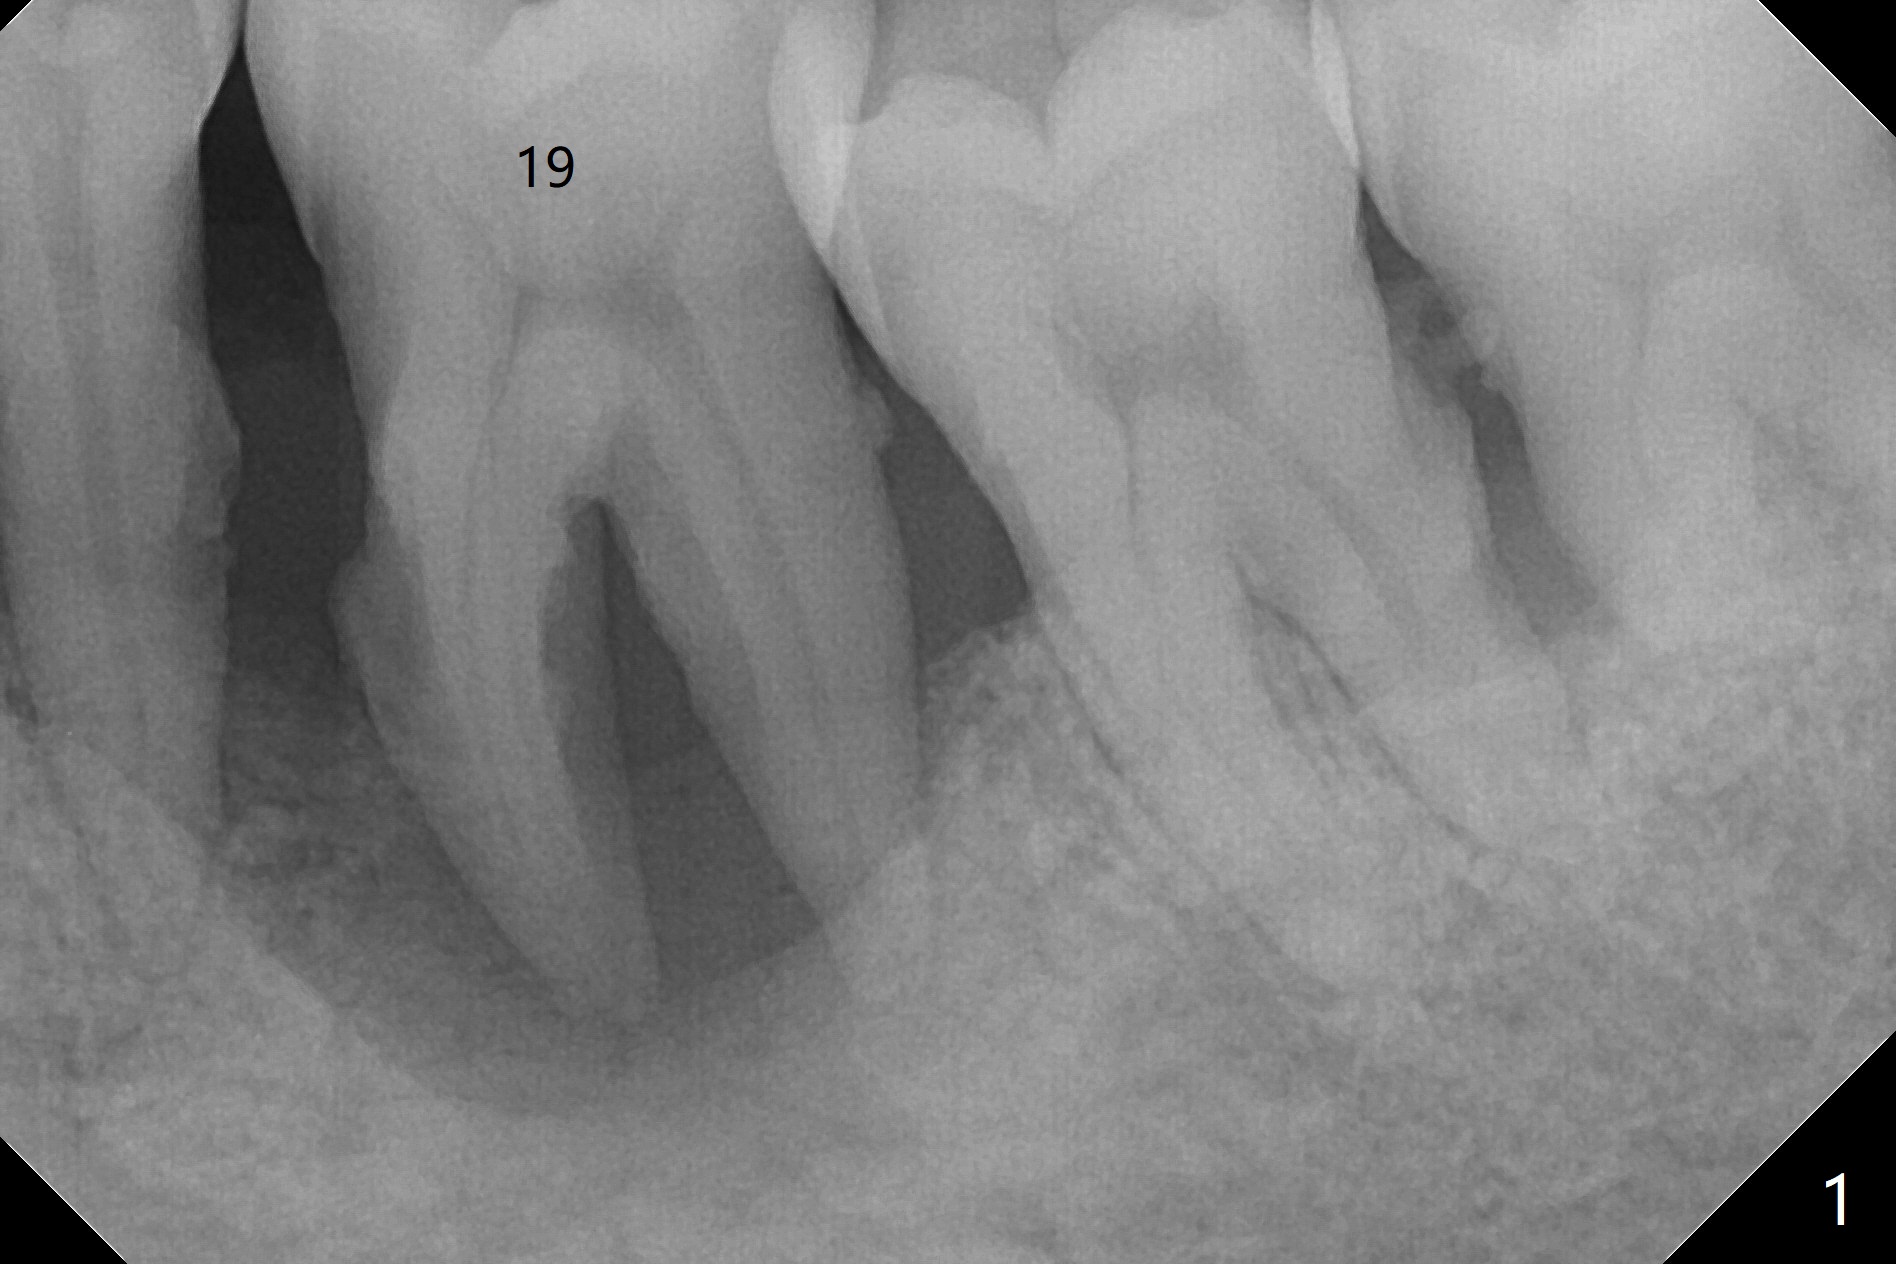

A 38-year-old man requests removal of the tooth #19 with mobility (Fig.1). With block anesthesia (more profound anesthesia than infiltration), SRP, extraction and socket preservation are conducted (Fig.2).